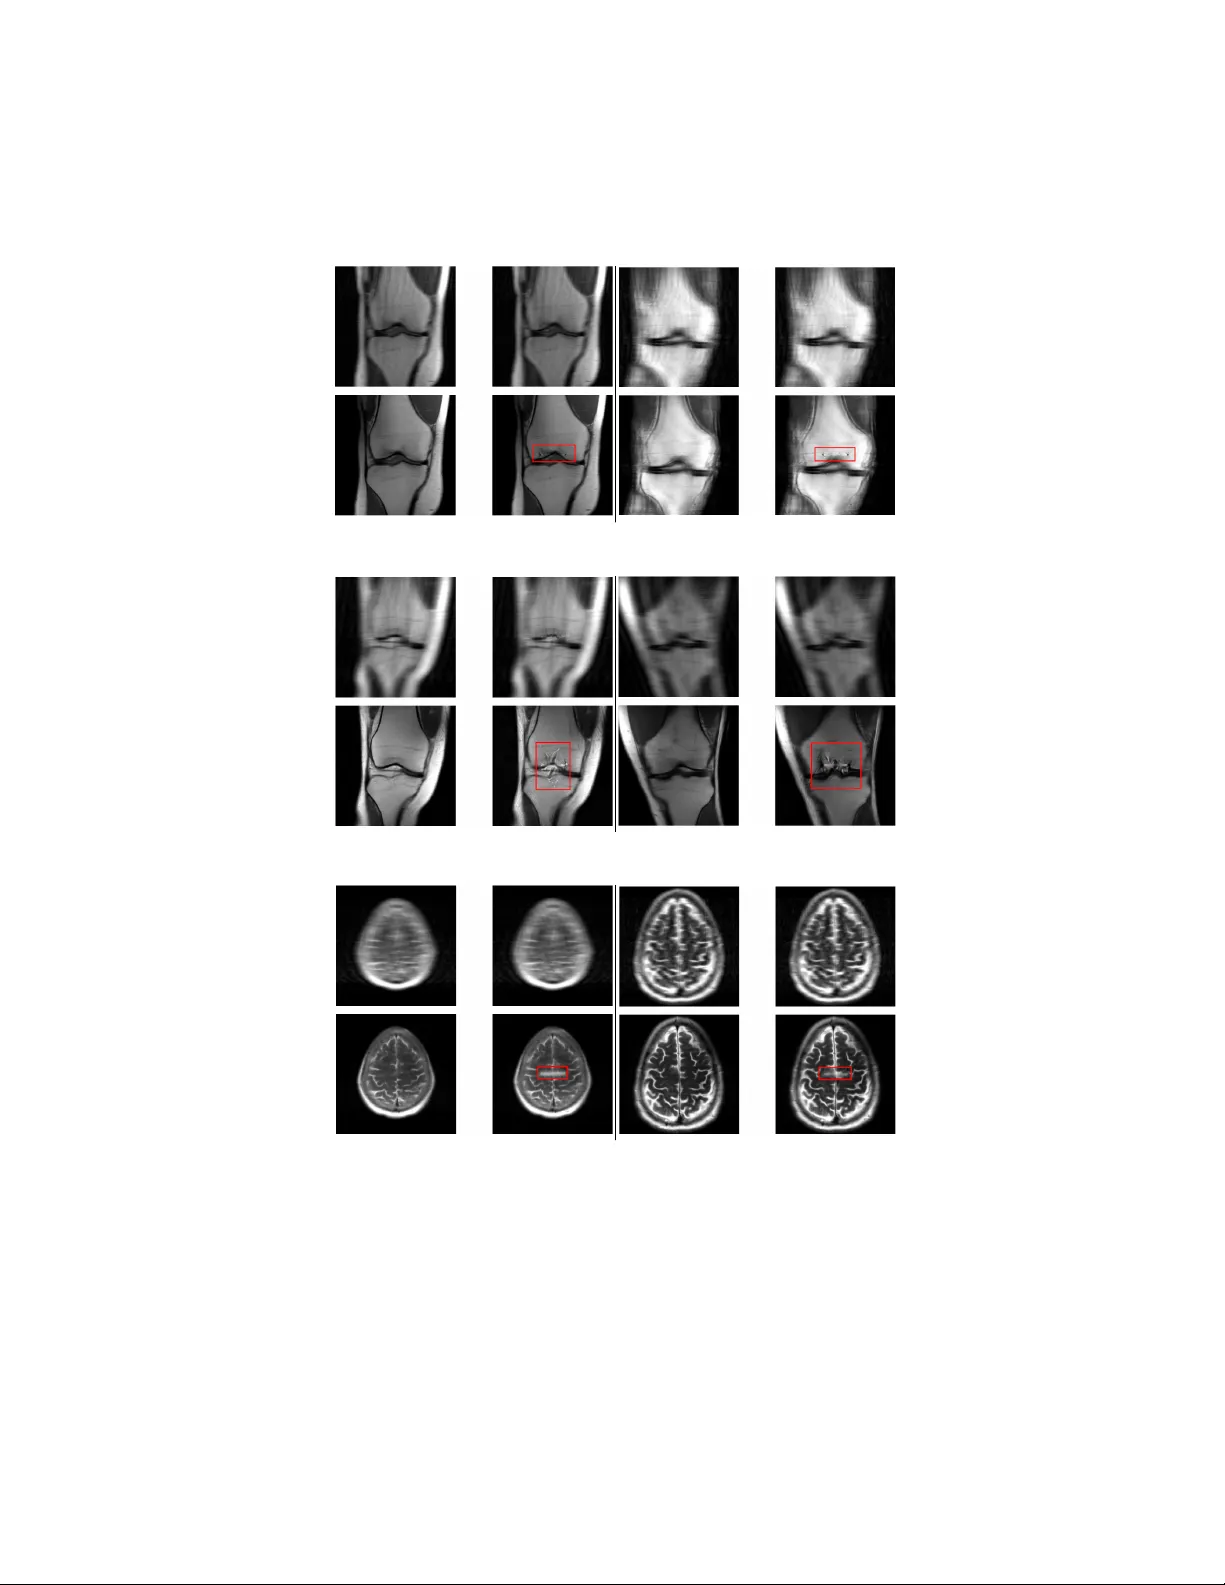

본 논문은 fastMRI 데이터셋의 뇌·무릎 영상을 대상으로 UNet과 E2E‑VarNet 재구성 모델에 미세한 적대적 교란을 가함으로써, 모델이 원본에 존재하지 않는 구조를 ‘환각’하게 만드는 취약성을 정량화한다. L∞ 제약 하에 거의 눈에 보이지 않는 교란을 설계하고, 목표 영역에 흰 선을 삽입하도록 유도한다. 실험 결과 PSNR·NRMSE·SSIM 등 전통적 품질 지표로는 환각 여부를 구분하기 어렵다는 점을 밝혀, 새로운 검출·방어 메커니…

실험은 fastMRI 데이터셋을 사용했으며, 단일 코일·다중 코일 무릎 영상과 다중 코일 뇌 영상을 대상으로 진행되었다. UNet과 E2E‑VarNet 모두 사전 학습된 체크포인트를 이용했으며, E2E‑VarNet은 단일 코일 무릎 영상에 대해서는 체크포인트가 없어 제외하였다. 교란을 적용한 후 재구성된 이미지에서는 목표 흰 선이 정확히 삽입되었으며, 이는 원본 이미지에 존재하지 않는 인위적 구조임에도 불구하고 인간 전문가가 구별하기 어려운 수준이었다.

품질 평가에서는 PSNR, NRMSE, SSIM을 각각 원본-교란 입력, 원본-교란 재구성 쌍에 대해 계산하였다. 결과는 정상 재구성과 교란 재구성 사이에 통계적으로 유의미한 차이가 없음을 보여준다. 즉, 전통적인 이미지 품질 지표는 환각을 감지하는 데 한계가 있다.